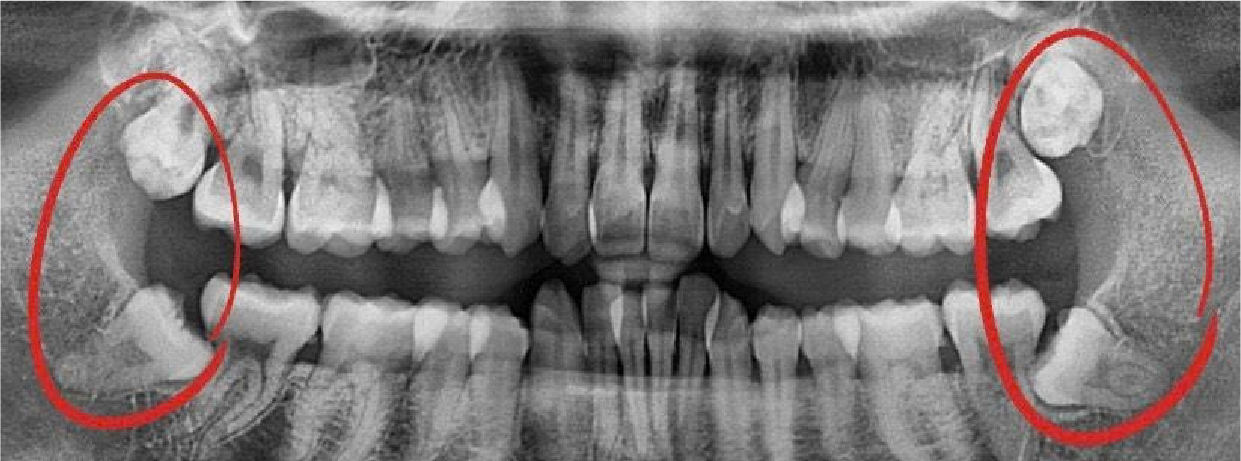

Bác sĩ kiểm tra tổng quát khoang miệng, chụp phim X-quang hoặc CT 3D để xác định vị trí, mức độ tổn thương và lập kế hoạch điều trị.

Hình Ảnh Trước & Sau Điều Trị

Minh chứng rõ ràng cho chất lượng và hiệu quả tại Nha khoa Như Ngọc – nơi mỗi khách hàng đều tìm lại được nụ cười tự tin sau quá trình điều trị và thẩm mỹ răng